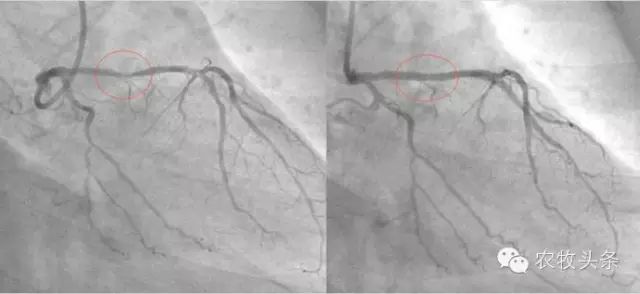

这位Hakim让他自己在家中做一个食疗,他吃了一个月。一个月后他去同一家医院做检查,发现三条血管干干净净,原来堵塞的地方已经全通了。为了让更多的人受益,他把自己的经验放在网上分享,他的前后两张血管照片也放了在网上,在照片中,服用食疗之前与之后的分别连普通人也看得出来。